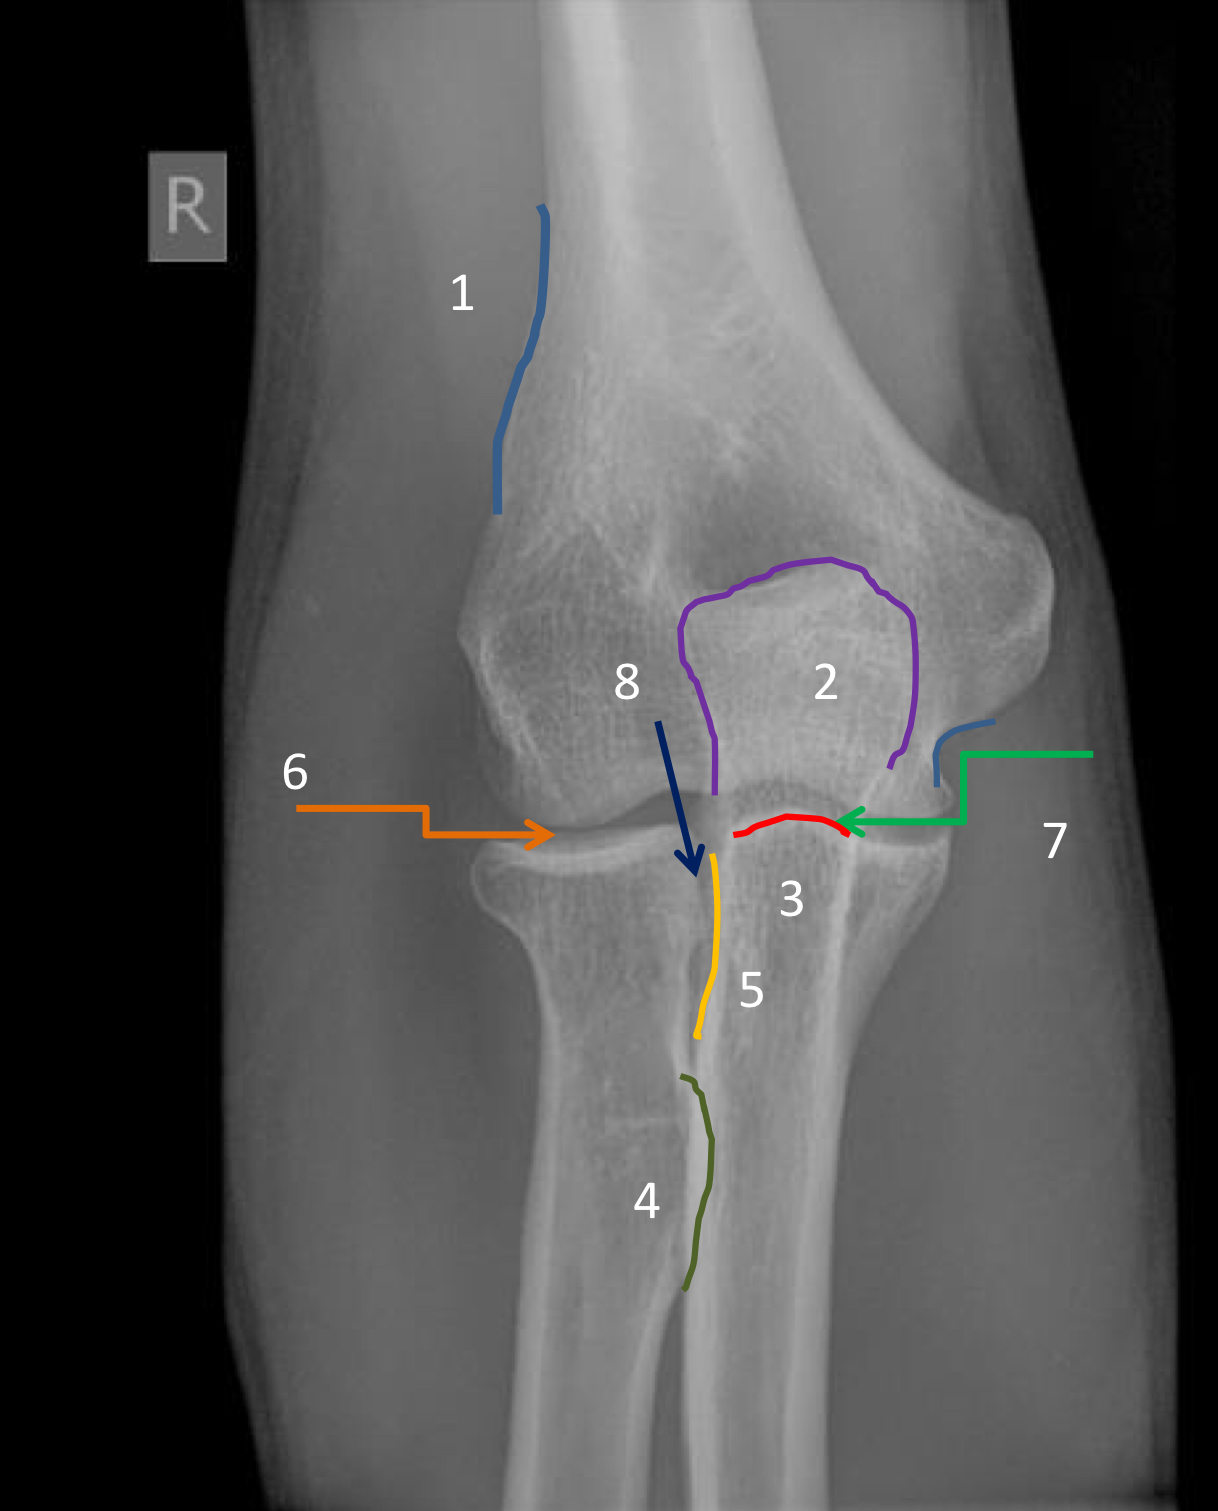

1?

olecranon fossa

2?

coronoid fossa

3?

olecranon process

4?

ulnar tuberosity

5?

capitellum

6?

trochlea

7?

trochlear notch

8?